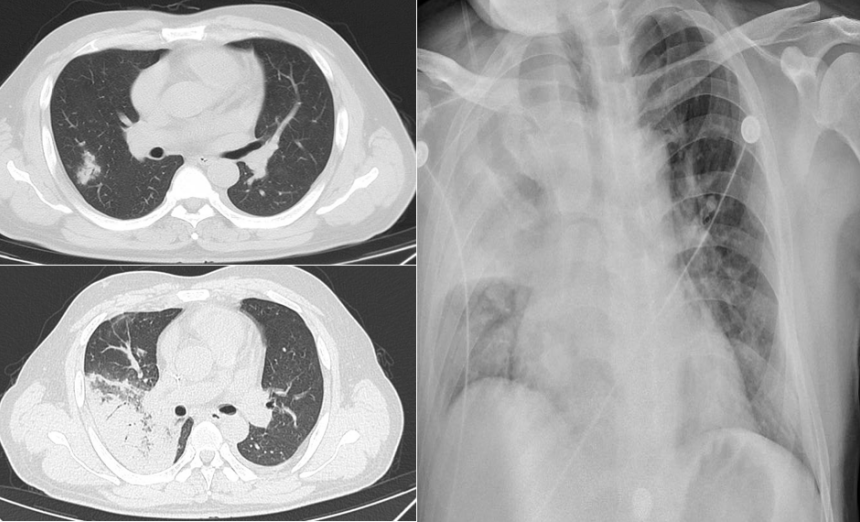

好发于用药后3个月,发热最常见,常是主要早期表现。呼吸道症状少,多以干咳为主,少见脓性痰。起病缓急差异极大,可以比较隐匿,也可突发起病,很快发展至严重呼吸衰竭,死亡率高。临床上常见的可快速进展至重症肺炎的病原体为耶氏肺孢子菌、巨细胞病毒、军团菌等。我中心曾收治一例成年女性患者,基础疾病为成人Still病,口服甲泼尼龙4个月,主诉“胸闷、呼吸困难4 d”,入住我院心内科,入院后诊断为“心衰”并进行相关处理,完善胸部CT检查可见双肺渗透性病变(图1),考虑呼吸困难原因为“肺部感染”,遂转入呼吸科治疗。转入呼吸科2天后,患者氧合迅速恶化,出现呼吸窘迫,氧合不能维持,于是转入RICU。转入当天再次复查胸部X线片发现双肺大面积渗出性病变(图1),最终诊断为PCP。该患者从发病到氧合不能维持行机械通气共7 d时间。另一例患者为中年男性,仓库保管员,以“发热”为主要诊断,入住血液科,基础疾病为初治的急性淋巴细胞白血病。入院第1天复查胸部CT可见右下肺少量片状渗出影(图2)。患者伴持续高热,予以常规抗G+菌及抗G-菌治疗,效果不佳。4 d后再次复查胸部CT发现肺部病变快速进展(图2)。患者出现严重呼吸窘迫,转入RICU。即刻完善气管镜检查,病原学提示军团菌,而此时患者已经出现极严重的呼吸窘迫,氧合不能维持,遂行气管插管接机械通气,最终病原学结果为军团菌。中年男性患者,基础疾病为肾病综合征,应用激素3个月,以“呼吸困难5 d”为主诉入院。胸部CT提示双肺弥漫性磨玻璃样渗出同时伴有大量结节(微小结节)(图3)。入院第2天紧急插管机械通气,最终病原学提示为巨细胞病毒感染。预测免疫受损宿主病死率的三个独立危险因素分别为:①疾病严重程度增加;②需要机械通气;③延迟诊断超过5 d以上。对于免疫受损宿主,早期诊断尤为重要,因其可以快速进展为重症ARDS。不同的氧合状况下,ARDS的诊疗策略不同。对于轻、中度ARDS,通常选择无创通气;对于中重度ARDS,通常以有创机械通气、俯卧位以及ECMO等进行呼吸支持。重症ARDS治疗的具体步骤和实施方法(简称“六步法”)如下: